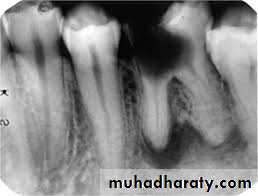

Radiographically, in the acute phase, no signs are observed at the bone (which may be observed 8–10 days later), unless there is recurrence of a chronic abscess, where upon osteolysis is observed.

Radiographic verification of a deeply carious tooth or restoration very close to the pulp, as well as thickening of the periodontal ligament, are data that indicate the causative tooth.

Phoenix abscesses demonstrate the outline of the original chronic lesion, with or without an associated ill-defined bone loss.